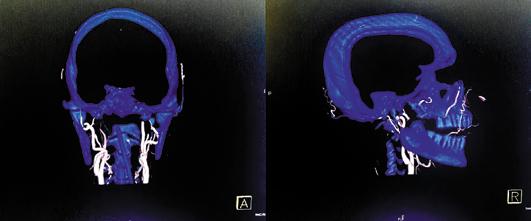

Por ello es que, para establecer el diagnóstico de muerte encefálica en nuestro país, debemos basarnos en lo estipulado en dos documentos que tienen el valor jurídico y legal para llevar a cabo todo el proceso conforme a derecho y dentro de los lineamientos éticos pertinentes. Uno de los documentos es la Ley General de Salud en sus artículos 343, 344 y 346, donde se establece lo necesario desde el punto de vista legal para la certificación de la pérdida de la vida a través del diagnóstico de muerte una imagen cerebral (por lo menos una tomografía de cráneo en fase simple) que muestre la causa de la muerte encefálica (edema cerebral grave, herniaciones, hemorragias graves, etc.).

•A nivel del mesencéfalo: Pupilas con falta de respuesta a la luz y con posición media con tamaño de 4 a 9 mm. La decorticación debe estar ausente. ►Una vez establecido el diágnostico clínico de la muerte encefálica es importante que los hallazgos sean corroborados por estudios de gabinete como lo indica el artículo 344 de la Ley General de Salud, en donde se solicita realizar un electroencefalograma (EEG), o bien, realizar un estudio que demuestre ausencia de flujo encefálico arterial, de los cuales el más utilizado es la angiografía por tomografía computada.

Ambos son accesibles, rápidos, de costo moderado y que permiten confirmar el diagnóstico para, de así requerirlo, continuar con el proceso de donación. La utilización de uno u otro dependerá de la disposición de estos en las unidades hospitalarias y de las condiciones de cada paciente.